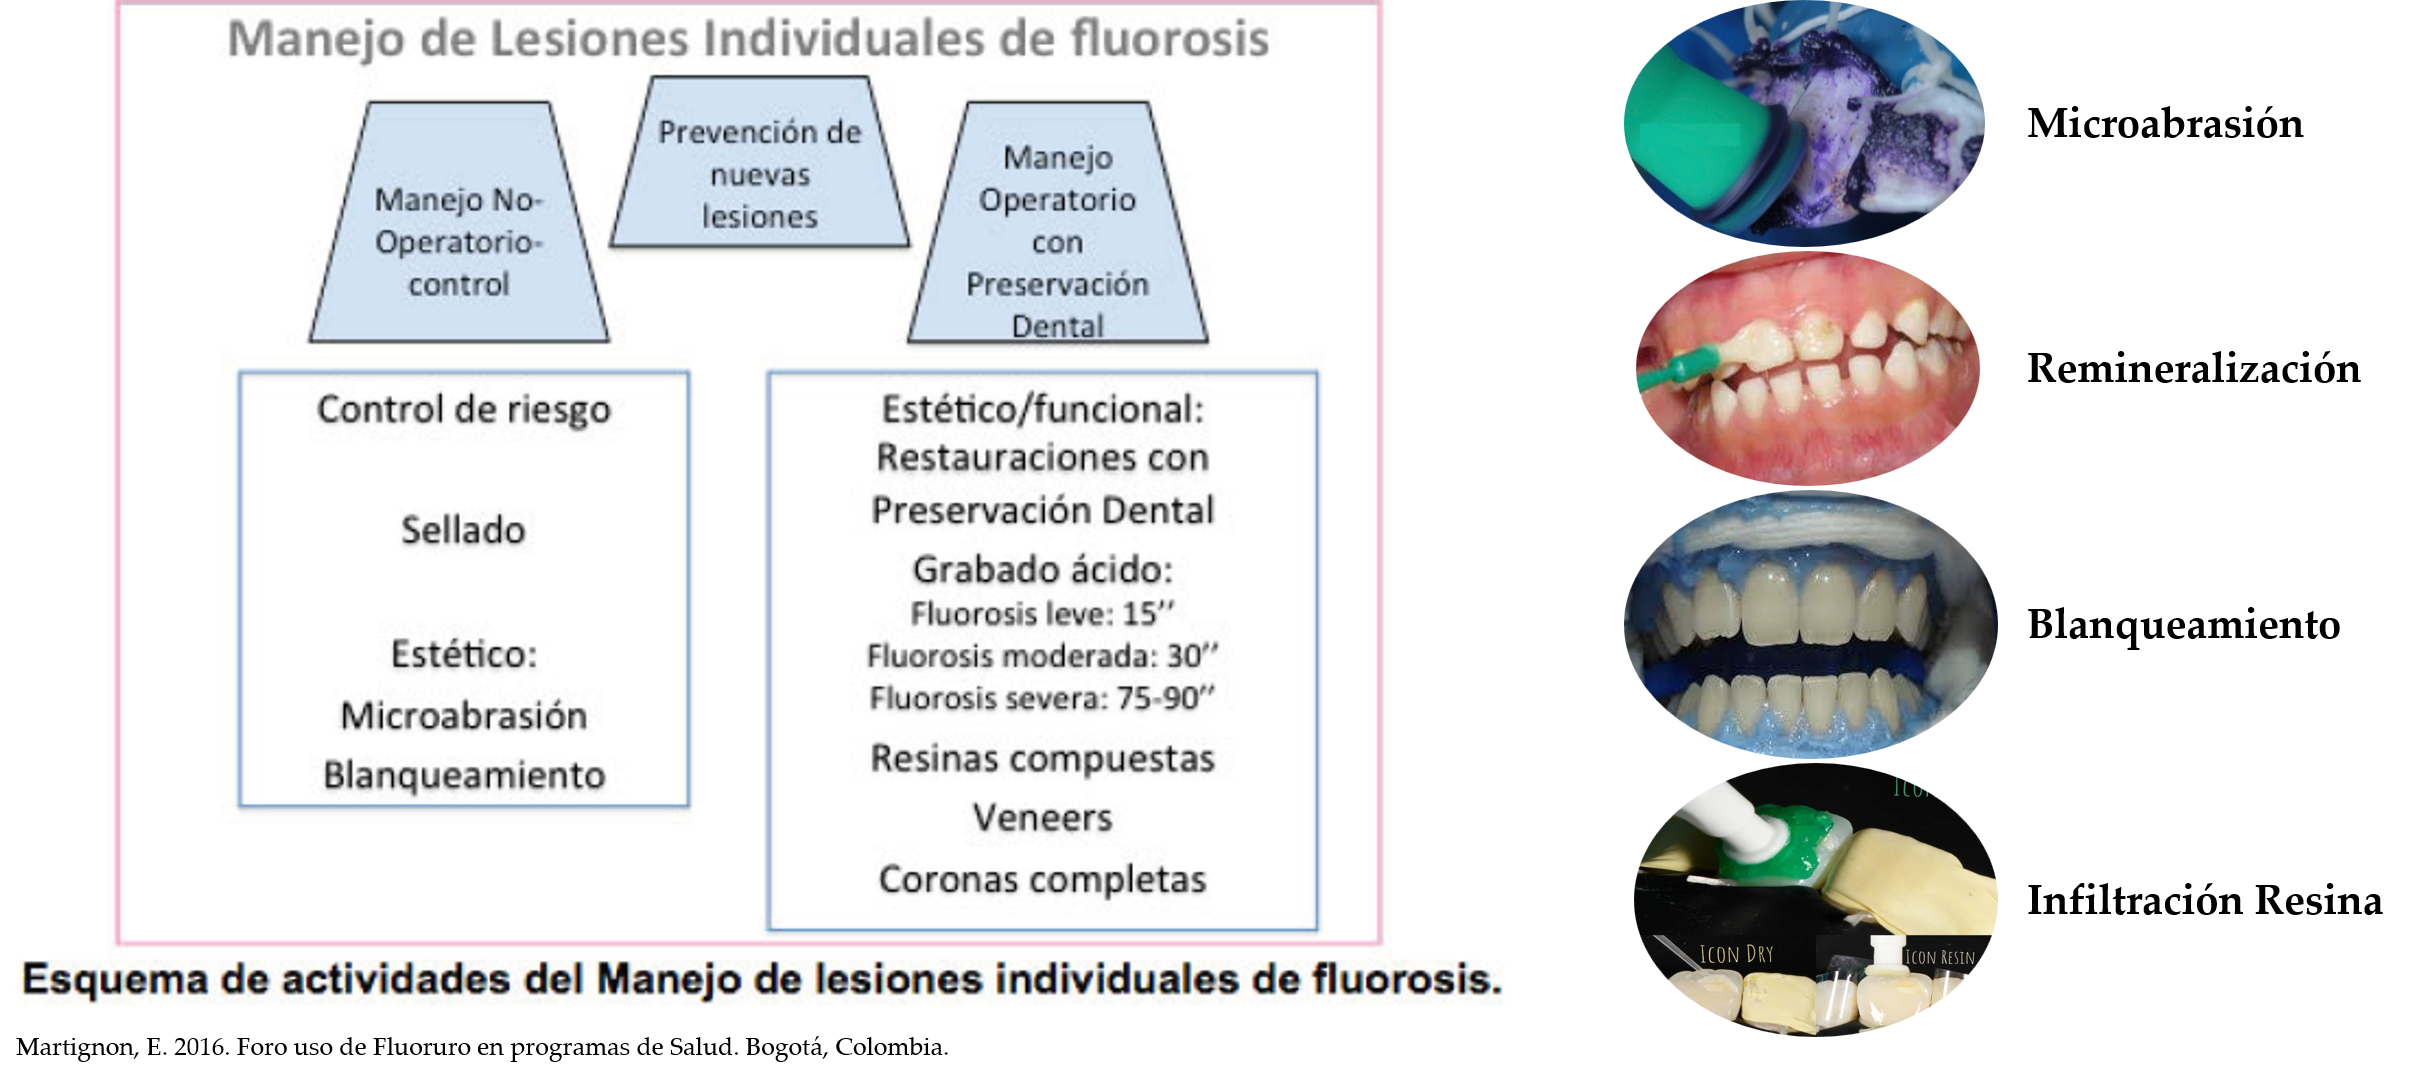

Manejo de lesiones de Fluorosis dental